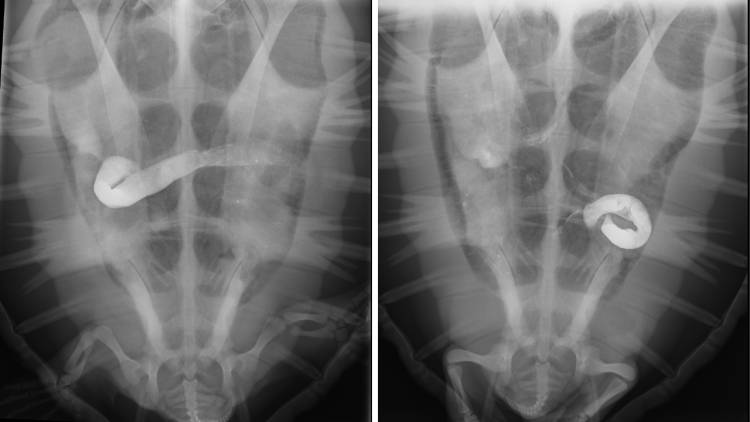

Barium studies allow the veterinary team to examine an animal's gut - something that would not normally be visible in X-ray images. Here we can see the isotope moving through Harry.

That's where X-rays come in. The Two Oceans Aquarium's veterinary clinic is at the disposal of the turtle team, who can use it to carry out a "contrast study" - a procedure where a turtle is fed a material (barium in our case) that reflects X-rays. This allows the team to see the fluid as it moves through a turtle's gut, and help find any internal injuries - allowing the team to make informed care decisions!